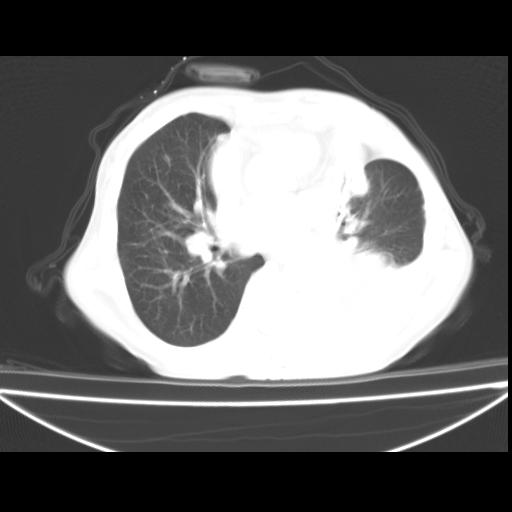

以下是引用zxl51642在2010-3-24 18:49:00的发言:[br]结合乳腺癌术后病史,考虑双肺及纵隔淋巴结多发转移、左侧胸膜转移并左侧大量胸水、左下肺膨胀不全。